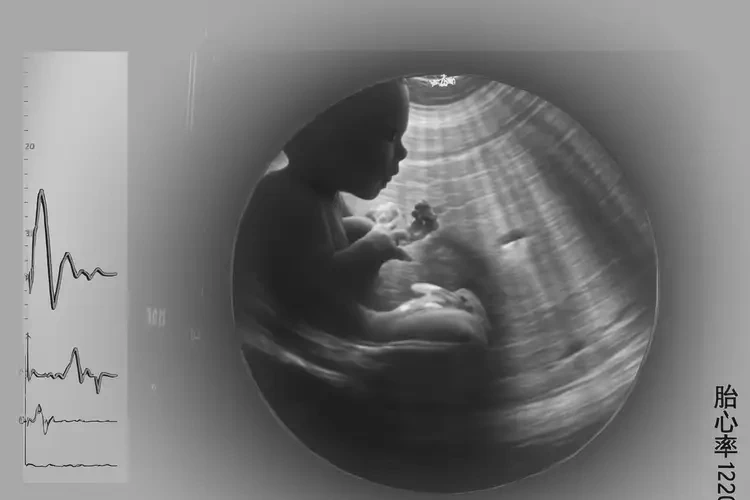

孕3周3天胎心100左右有危險嗎(圖1)